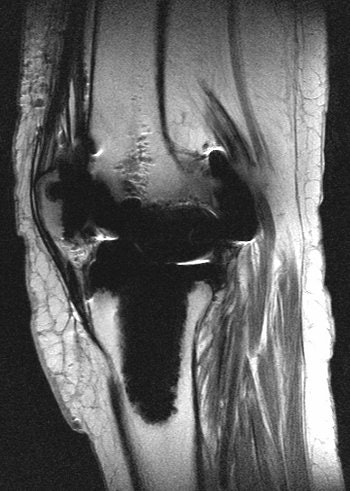

| MR scans of a 58-year-old woman with catastrophic hip failure. |